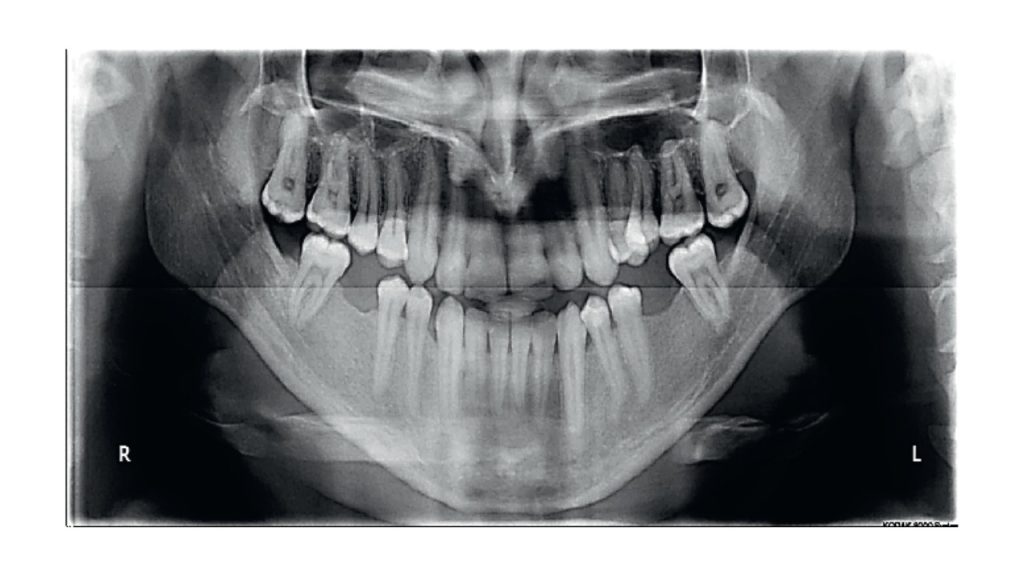

Streszczenie: Ciężka wada zgryzu klasy III może być dużym wyzwaniem, zwłaszcza u pacjentów dorosłych. W niniejszej pracy kazuistycznej przedstawiono przypadek dorosłego pacjenta z ciężką szkieletową wadą zgryzu klasy III, z ewidentnym niedorozwojem szczęki i nadmiernie rozwiniętą żuchwą, co powodowało zgryz krzyżowy przedni i tylny, a także przesunięcie linii środkowej górnego i dolnego łuku zębowego w lewo względem linii środkowej twarzy. Sytuację komplikowały mechanizmy kompensacyjne, takie jak proklinacja siekaczy górnych i retroklinacja siekaczy dolnych. Przeprowadzono dekompensację łuku górnego i dolnego w połączeniu z poszerzeniem łuku górnego w celu zmniejszenia stłoczenia w łuku górnym i skorygowania zgryzu krzyżowego tylnego. Następnie przeprowadzono osteotomię Le Fort I w obrębie szczęki i obustronną osteotomię strzałkową (BSSO) w obrębie żuchwy, po czym metodami ortodontycznymi skorygowano wszelkie inne rozbieżności zębowe. Uzyskano znaczącą poprawę estetyczną i funkcjonalną, przy dużym zadowoleniu pacjenta.

Summary: Severe class III malocclusion can be a great challenge, especially in adult patients. This case report describes an adult patient [...]